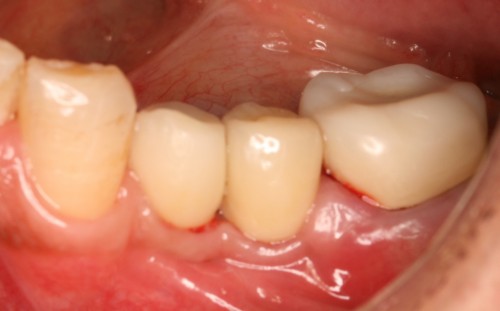

術前

被せ物装着

同全体写真